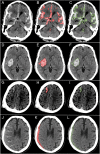

Computed tomography (CT) of the head is used worldwide to diagnose neurologic emergencies. However, expertise is required to interpret these scans, and even highly trained experts may miss subtle life-threatening findings. For head CT, a unique challenge is to identify, with perfect or near-perfect sensitivity and very high specificity, often small subtle abnormalities on a multislice cross-sectional (three-dimensional [3D]) imaging modality that is characterized by poor soft tissue contrast, low signal-to-noise using current low radiation-dose protocols, and a high incidence of artifacts. We trained a fully convolutional neural network with 4,396 head CT scans performed at the University of California at San Francisco and affiliated hospitals and compared the algorithm's performance to that of 4 American Board of Radiology (ABR) certified radiologists on an independent test set of 200 randomly selected head CT scans. Our algorithm demonstrated the highest accuracy to date for this clinical application, with a receiver operating characteristic (ROC) area under the curve (AUC) of 0.991 ± 0.006 for identification of examinations positive for acute intracranial hemorrhage, and also exceeded the performance of 2 of 4 radiologists. We demonstrate an end-to-end network that performs joint classification and segmentation with examination-level classification comparable to experts, in addition to robust localization of abnormalities, including some that are missed by radiologists, both of which are critically important elements for this application.